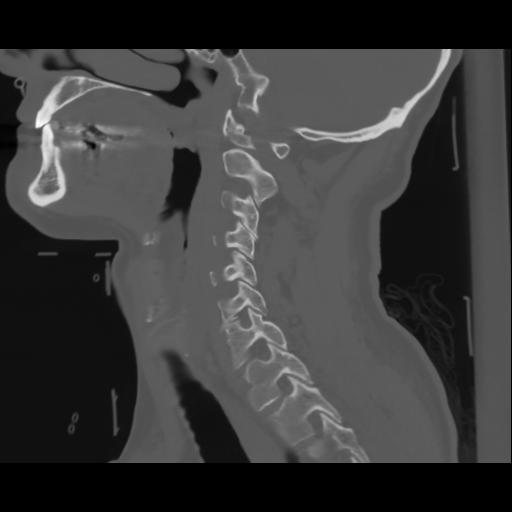

14 P.BLANDAS,,Sagittal,2.000,P.BLANDAS,Sagittal,